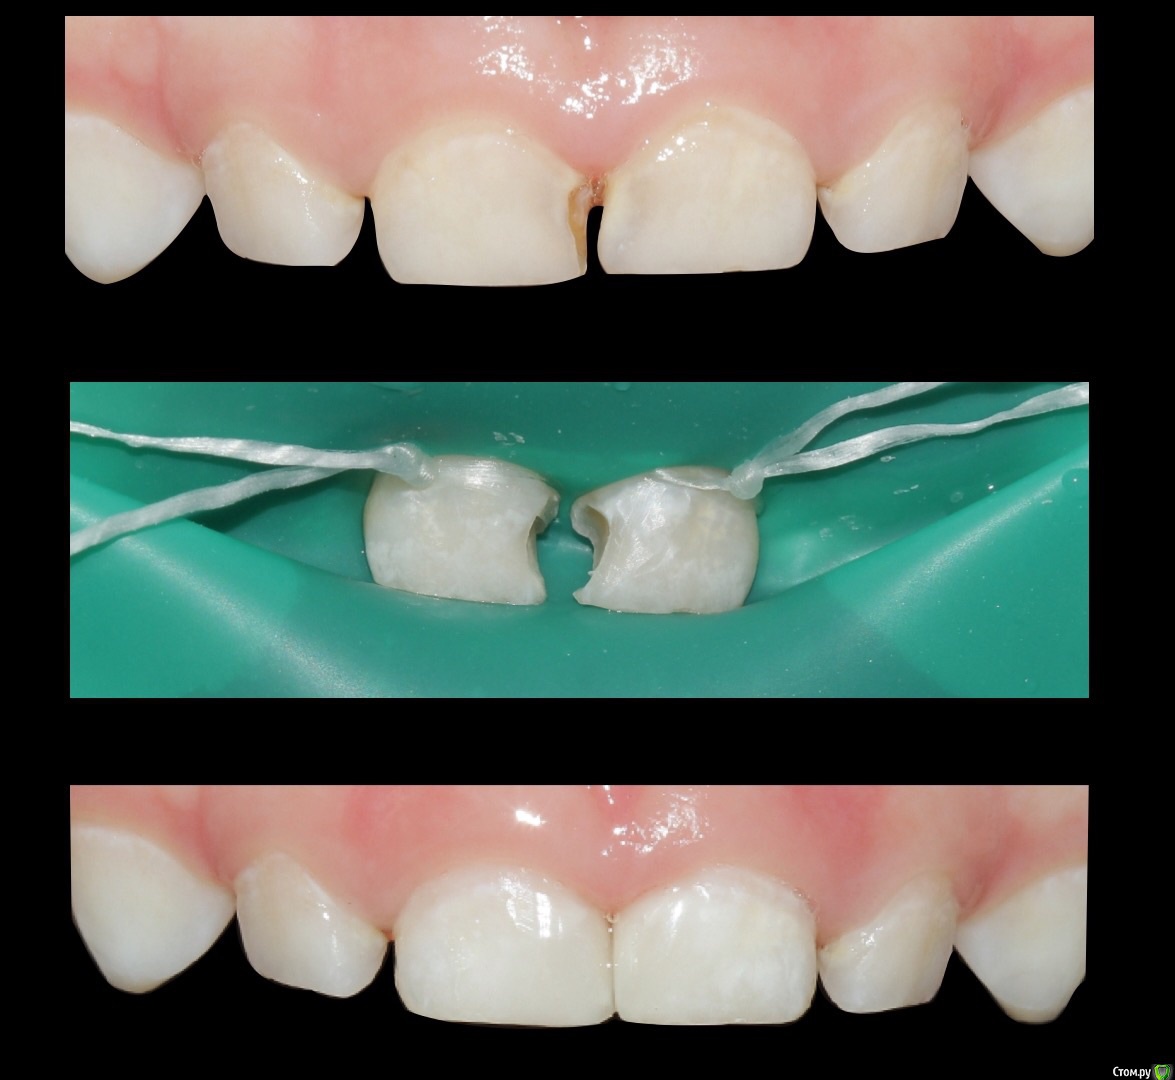

Екатерина Геранина Опубликовано 27 ноября, 2015 Поделиться Опубликовано 27 ноября, 2015 Возраст-не противопоказание ))) 3 года 2 Ссылка на комментарий

Джима Опубликовано 27 ноября, 2015 Поделиться Опубликовано 27 ноября, 2015 по-моему, на 5.1 лигатура съехала Ссылка на комментарий

Екатерина Геранина Опубликовано 27 ноября, 2015 Поделиться Опубликовано 27 ноября, 2015 по-моему, на 5.1 лигатура съехала Да, я увидела после фоторегистрации , приступив к работе. Затянула щадяще. Но потом все поправила Ссылка на комментарий

CRAZYDUCK Опубликовано 27 ноября, 2015 Поделиться Опубликовано 27 ноября, 2015 Катя , а клампов не видно , без них , только на лигатурах держится ? В 51 пульпа вскрылась ? Ссылка на комментарий

Екатерина Геранина Опубликовано 29 ноября, 2015 Поделиться Опубликовано 29 ноября, 2015 Катя , а клампов не видно , без них , только на лигатурах держится ? В 51 пульпа вскрылась ?Да, без клампов. Платок на рамку несильно натягивали, поэтому все хорошо держалось. Не вскрылись Ссылка на комментарий